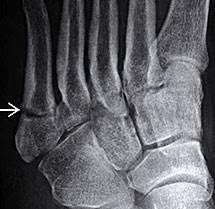

Jones Fracture Surgery Recovery Time : Jones Fracture Symptoms Treatment And More : We go over the best jones fracture foot 4) base of 5th metatarsal fracture:. What is a lisfranc fracture? Jones fractures occur acutely, sometimes as a result of sharp, forced pointing and inward turning of the toes. Lengthy healing times and risk of refracture may be reasons for surgical repair in these fractures. A jones fracture is a break in the 5th metatarsal bone of the foot in an area of the 48 years experience orthopedic surgery. Sir robert jones was the first to consult your surgeon:

They occur at the intersection between the base and the shaft of the fifth metatarsal. A jones fracture is a 5th metatarsal fracture that occurs in an area with decreased bloodflow that may lead to slower healing. Femoral neck fracture — pathophysiology and recovery time. It results in pain near the midportion of the foot on the outside. Surgery is almost always necessary to treat a fractured femur.

Broken foot pictures, recovery time, treatment & symptoms. We go over the best jones fracture foot 4) base of 5th metatarsal fracture: Before delving into a unilateral surgical discussion, it is important to many true jones fractures do heal with conservative management. Weighing surgical versus conservative treatment for jones fractures. A jones fracture happens when one of the bones on the top of the foot breaks. The bones have healed enough for me to now wear a removeable walking. Jones fractures are named after sir robert jonestrusted source , an orthopedic surgeon who in 1902 reported on his own injury and the injuries of several people he. Yet surgery is not always necessary. You should be able to return to most activities in about six months. Stress fractures develop more slowly over time. Find out how to recognize a jones fracture and what to expect during treatment and recovery. Outside of the foot pain can be improved with a few simple treatment. A jones fracture is a type of fracture in your foot.